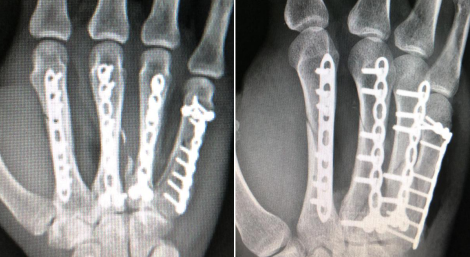

由于蒋先生右手第2-5掌骨均为粉碎性骨折,手术难度非常大,熊医生手术团队经讨论决定为蒋先生掌骨骨折行钢板内固定,使用钢板内固定不但固定牢靠,而且可在早期行功能康复锻炼,更有利于右手的功能恢复,对患者以后日常生活影响较小。而右示指中节指骨骨折选择钢针内固定,优点在于损伤小,占位少,针尾可露于皮外,术后复查骨折的愈合良好,可取出钢针。

明确手术方案后,第二天熊祖国医生为蒋先生安排了手术,术中手法复位右示指骨折端,钢针内固定,右手桡背、尺背侧各做了切口,复位右手第2-5掌骨骨折端,各植入金属接骨板、螺钉固定,术中一切顺利。术后复查右手X线片,见各骨折复位良好,内固定在位,乍一看,如同“钢筋铁骨”。

术后即刻